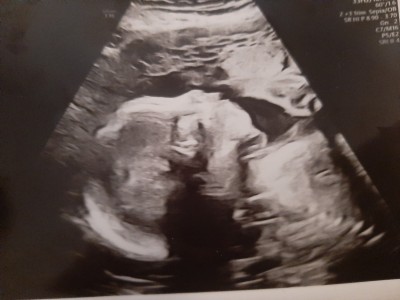

Daha net olan resim kaybettiğim kızımın 23 haftalik hali

Bulanık olan ise bugün çekildiğimiz 26 haftalik kızımın resmi

Bulanık çıkartıyor makine o yüzden mi acaba böyle image

sarı halka kafasi mavi halka burnu mavi ile Ok yaptigim da agzi acik duruyor